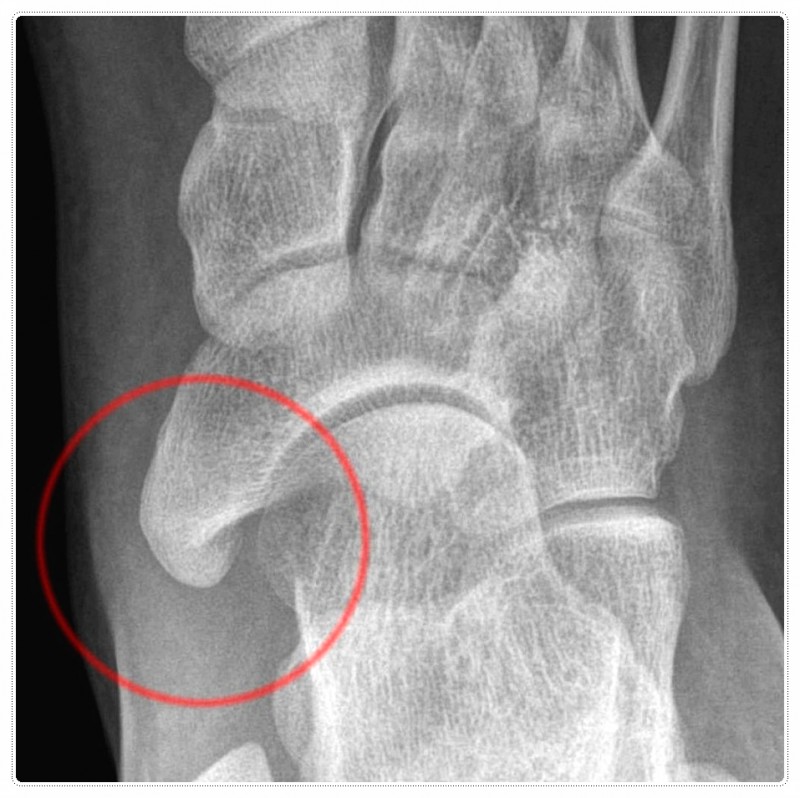

특히 골절의 정도가 심했거나 인대 파열이 함께 있었던 경우라면, 우리 몸은 스스로를 보호하기 위해 주변 근육을 단단히 굳게 만듭니다.